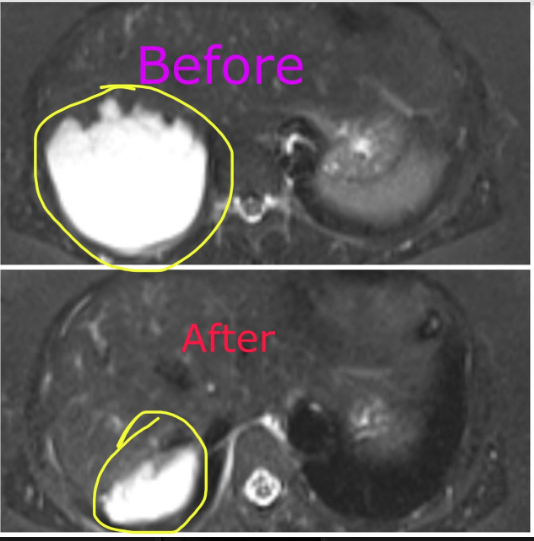

2. CT Scan or MRI Scan

Embolisation For Liver Hemangiomas

Through a small prick in a thigh or arm blood vessels , catheters are tracked into the blood vessels feeding the hemangioma.

Treatment is administered into the haemangioma directly.

The tumor then shrinks over time , will complete resolution of symptoms.

One year follow up below , 90 % shrinked , the rest will shrink with time , and we lose nothing giving it time to completely shrink , all symptoms (pain in this case) resolved after treatment (embolisation ).